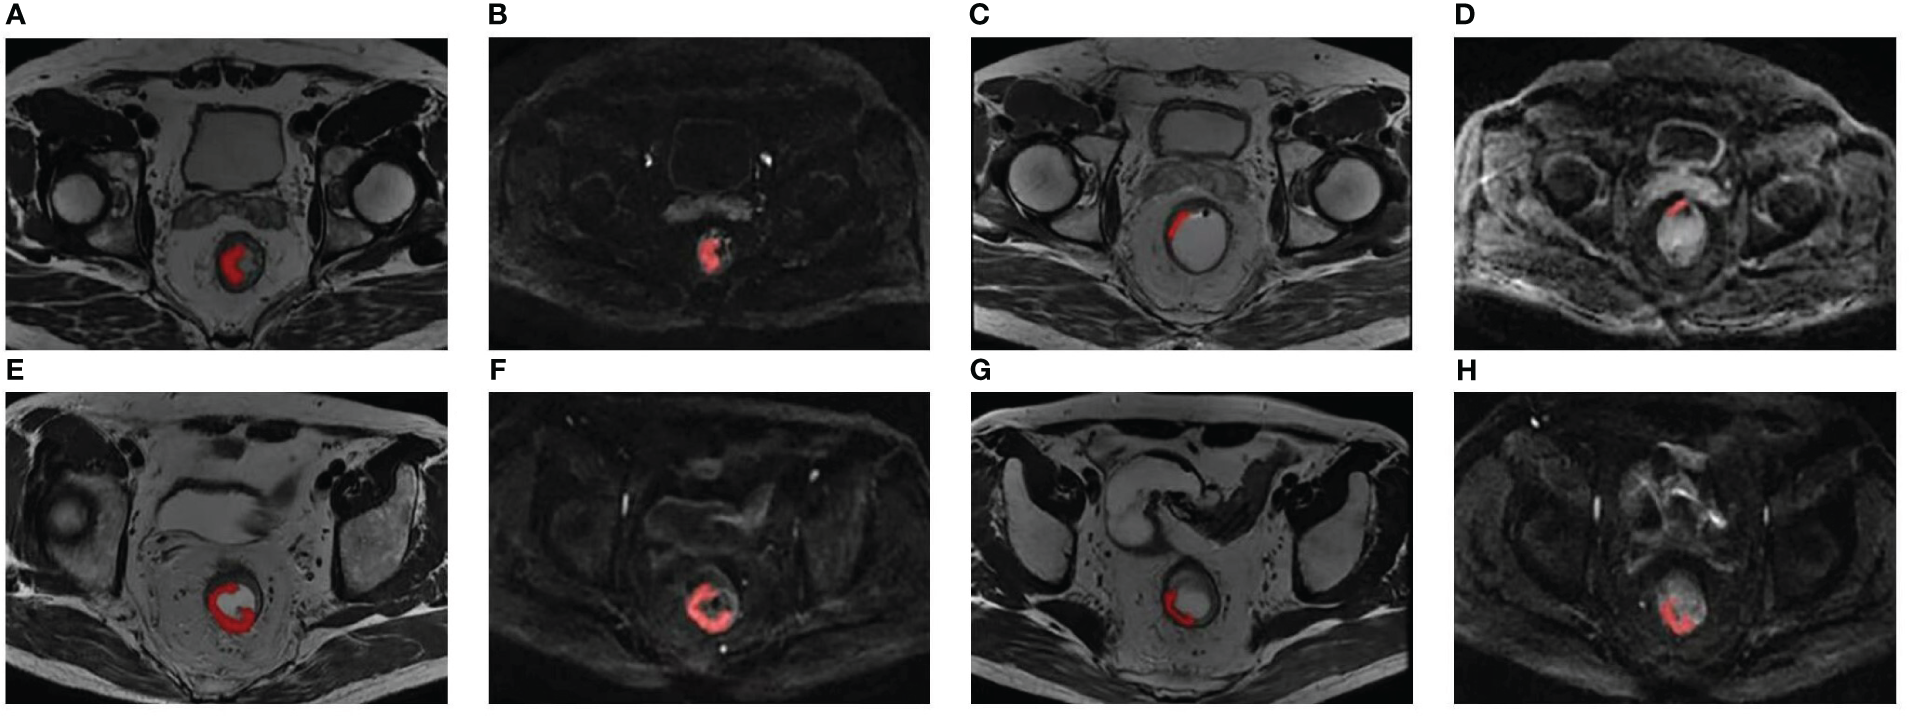

The delineation of regions of interest (ROIs) and radiomic feature extraction were performed on the pre- and posttreatment oblique axial T2WI and axial DWI by using Radcloud version 3.1.0, which was based on the “pyradiomics” package within Python version 3.8.1. Reader 1 (a junior radiologist with three years’ diagnostic experience in gastrointestinal imaging) and reader 2 (a senior radiologist with 16 years’ diagnostic experience in gastrointestinal imaging) conducted a review of each imaging set to reach a consensus over the ROIs. Reader 1 first drew manually on each consecutive tumor-containing slice, which showed intermediate T2WI and high DWI signal in contrast with the normal signal of the muscular layer of the adjacent rectal wall. In some patients, tumor signals were not identified on posttreatment images, and these ROIs were positioned at the location of the tumor bed before treatment (21). Figure 1 shows two examples of segmentation of ROIs on the pre- and posttreatment images. Reader 2 then examined these ROIs. The two readers would discuss to reach a consensus if there was a discrepancy. They were unaware of the pathological results and clinical data. Imaging normalization weighting coupled with resampling for voxel size (1×1×1 mm3) was conducted. Radiomic feature extraction was followed by an automatic procedure. The types of features are listed in Supplementary Table S2. There were 1,409 parameters extracted from each modality and 5636 parameters in total were extracted for each patient.

Figure 1

Two examples of segmentation of ROIs on the pre- and posttreatment images. Panels (A-D) show the segmentation of a 51-year-old patient with low-rectum adenocarcinoma at a stage of cT3N1M0. (A, B) Pretreatment oblique axial T2WI and axial DWI (b = 1000 s/mm2); (C, D) Posttreatment oblique axial T2WI and axial DWI (b = 1000 s/mm2); this patient was demonstrated pCR by surgical pathology. Panels (E-H) show the segmentation of a 60-year-old patient with low-rectum adenocarcinoma at a stage of cT3N1M0. (E, F) Pretreatment oblique axial T2WI and axial DWI (b = 1000 s/mm2); (G, H) Posttreatment oblique axial T2WI and axial DWI (b = 1000 s/mm2); this patient was demonstrated non-pCR by surgical pathology. DWI, diffusion-weighted imaging; pCR, pathological complete response; ROI, region of interest; T2WI, T2-weighted imaging.